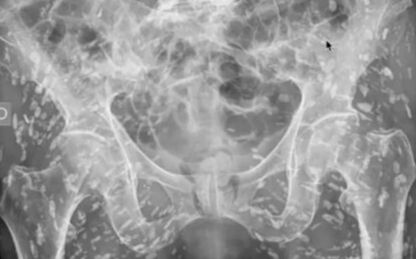

Người đàn ông quyết định đến bệnh viện kiểm tra sức khỏe sau khi trải qua cơn đau hông dữ dội.